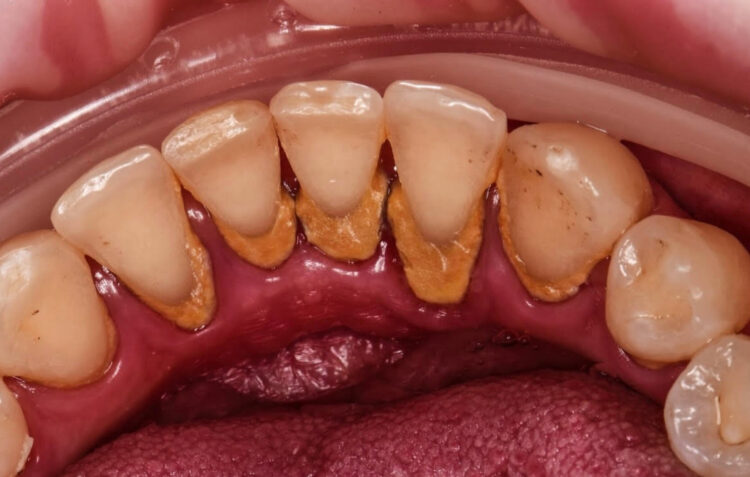

①歯石とは。

歯についた日頃の汚れ(プラーク)が長く放置されていて石灰化された乳白黄色の硬い石のようなもの。

②歯石はそもそもなぜついてしまうのか。

歯ブラシやフロスでのお掃除不足が主な原因ですが、

唾液の中のカルシウム濃度が高かったりタバコなどで着色がつき表面のざらつきによって

プラークがつきやすく石灰化しやすかったり、

歯並びが影響でつきやすい環境化の方もいらっしゃいます。

③歯石はなぜ取ったほうが良いのか。

歯石を放置してしまうとみるみる歯茎が発赤し、炎症によってもっと進行してくると

骨が溶け出して歯茎が下がり最終的には歯がぽろっと抜け落ちてしまう恐れがあります。

また歯石は口臭の原因にもなります。